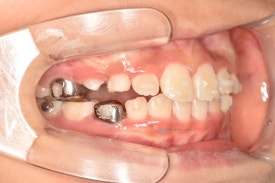

치료 전 - 위아래 심한 공간 부족이 관찰됩니다.

아이는 위 아래 심한 공간부족으로 인한 어린이덧니가 관찰됩니다. 공간부족으로 인해 앞니가 삐뚤빼뚤하게 나왔으며 곧 나올 위 두번째 앞니도 회전되어 맹출이 예상됩니다.

투명교정장치의 장점을 고려하여 어린이교정을 투명교정장치로 시작하였습니다. 아이의 협조도가 매우 좋아 하루가 다르게 예뻐져서 오네요!